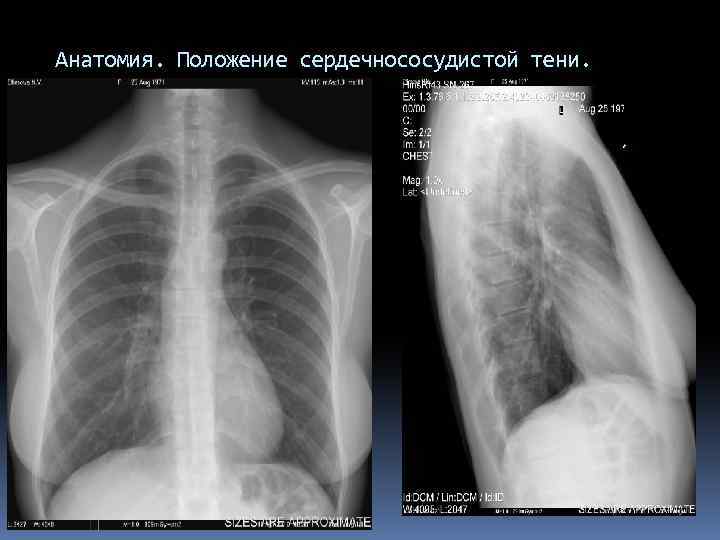

Анатомия. Положение сердечнососудистой тени.